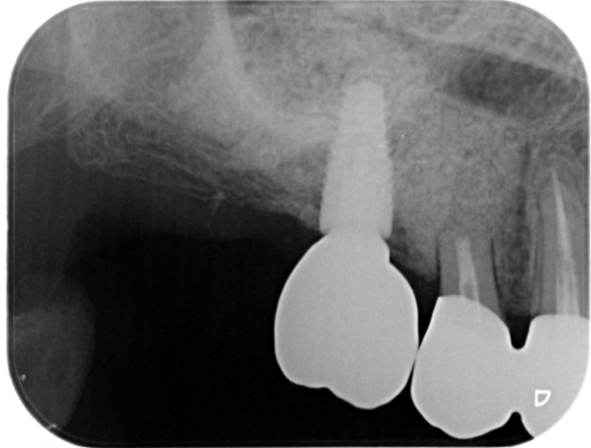

症例3

| 項目 | 詳細 |

|---|---|

| 患者様データ | 68歳 女性 |

| 来院時の主訴 | 「普通に食事がしたい。」 |

| 医院の診断 | 歯牙欠損、重度の顎堤欠損、角化歯肉不足 |

| 通院期間 | 10か月 |

| 来院回数 | 15回 |

| 治療費 | 総額:1,005,000円(税抜) 【内訳】 GBR(骨再生手術)250,000円、インプラント埋入手術250,000円、2次手術+FGG(遊離歯肉移植術)55,000+60,000円、仮歯30,000円、インプラント上部構造(セラミッククラウン)170,000円、歯冠長延長術70,000円、セラミッククラウン120,000円 |

| リスクと副作用 | 定期的なメンテナンスが必要、術後若干の腫れと痛み |

| ここがこだわりのポイント!☝ | 骨量不足により他院にてインプラントを断られた患者様です。大規模な骨造成を行うことでインプラント治療が可能になりました。 |